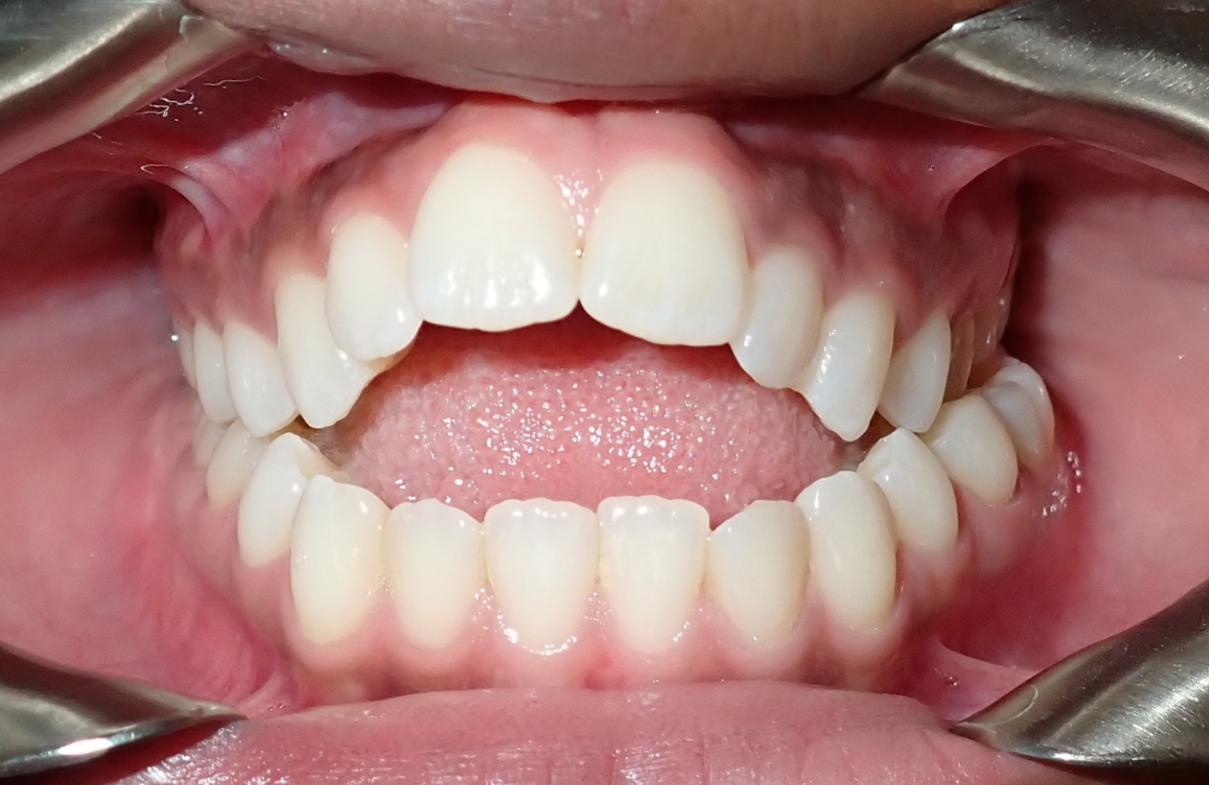

Close-up of a person's mouth showing braces on the upper and lower teeth, with some braces having pink bands.

Ortodoncia para adultos

Nunca es tarde para amar tu sonrisa. Muchas personas adultas eligen el tratamiento de ortodoncia como una manera efectiva de mejorar su confianza y su salud oral.